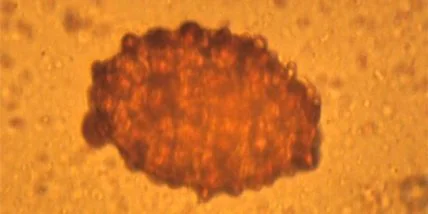

Ученые из Кембриджа исследовали под микроскопом остатки фекалий, сохранившиеся на деревянных палочках (эти объекты в древности выполняли функцию туалетной бумаги). Палочки извлекли из уборной, которая использовалась с 111 года до нашей эры по 109 год нашей эры. В пробах нашли яйца четырех видов гельминтов - аскариды, власоглава, свиного цепня и китайской двуустки.

Отмечается, что последнему паразиту для завершения жизненного цикла нужны влажные, заболоченные области. Однако обследованный караван-сарай находится на краю пустыни Такла-Макан — в высшей степени засушливом месте.

Паразит мог попасть туда только из внутренних районов Китая (например, Гуандуна). То есть яйца двуустки стали очевидным доказательством того, что Великий шелковый путь был каналом передачи болезней по Евразии.